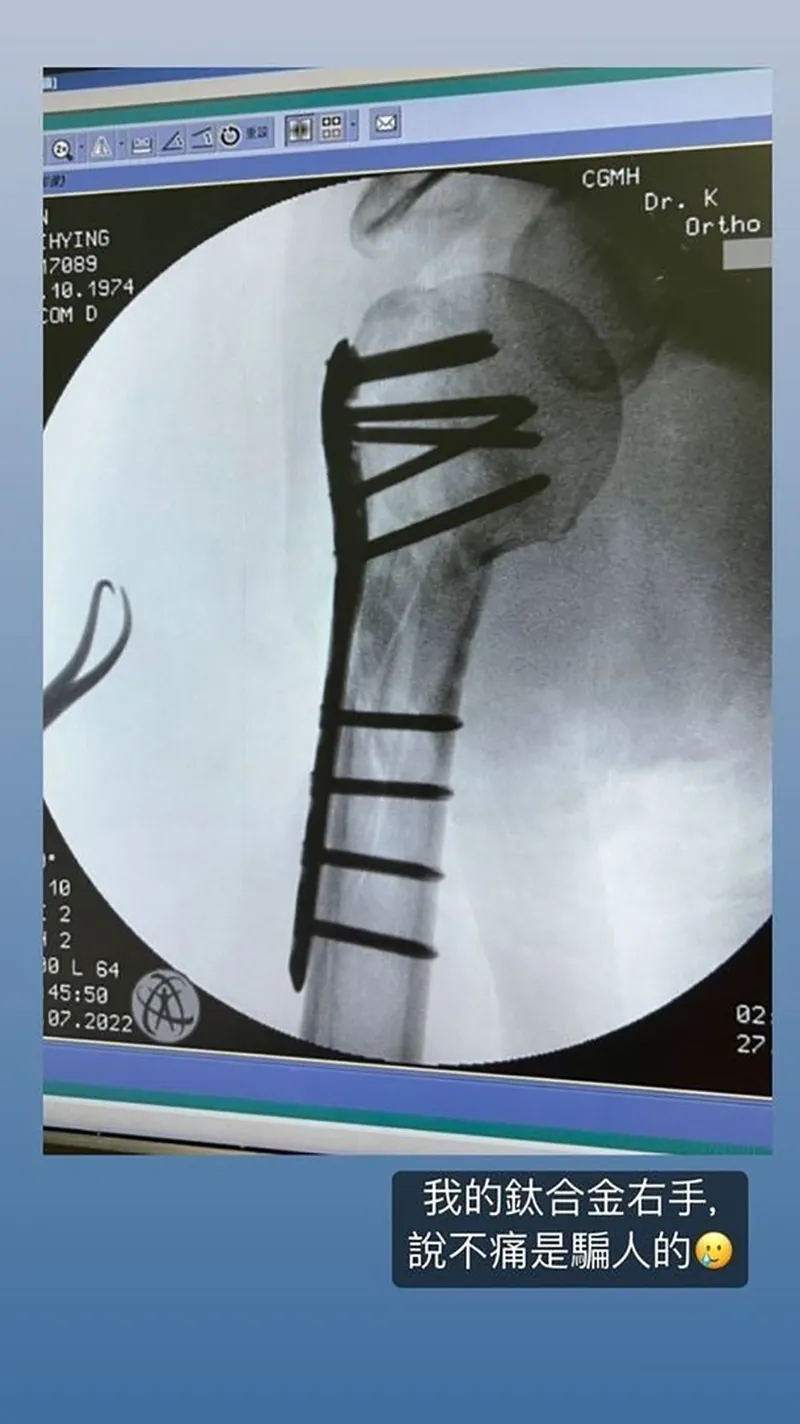

Anh phải phẫu thuật cố định cánh tay

Tháng 7/2022, truyền thông Hoa Ngữ chấn động trước bố con Lâm Chí Dĩnh gặp tai nạn xe cộ thương tâm trên đường. Theo hình ảnh được ghi lại, chiếc xe của Lâm Chí Dĩnh cháy rụi phần đầu sau khi va chạm. May mắn là Lâm Chí Dĩnh và con trai Jenson đều được đưa đi bệnh viện kịp thời. Sao nam đình đám được chẩn đoán rạn xương mặt, gãy xương bả vai và chấn thương sọ não nhẹ. Lâm Chí Dĩnh được phẫu thuật đóng 10 chiếc đinh và một tấm hợp kim titan lên xương tay để tái tạo cấu trúc. Sau khi hồi phục, Lâm Chí Dĩnh vẫn tiếp tục tập vật lý trị liệu cùng chuyên gia y tế để cử động tay bình thường.